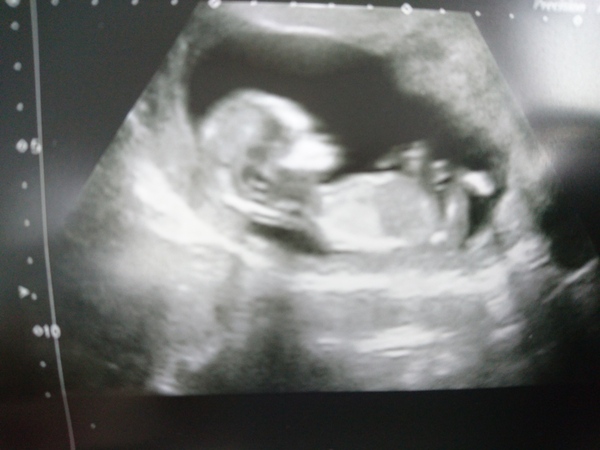

Very very wriggly baby. Was changing sides, somersaulting, turning its back to us, flipping upside down, everything but staying still. No nuchal fold measurements taken. Was in there for over half an hour and my belly feels battered. But a healthy and active baby which was good to see. Edd now 10 Dec. Couldn't see nub either.

Good pics though @Royalsteph 😄 Pleased for you

Great scan piccie Steph x